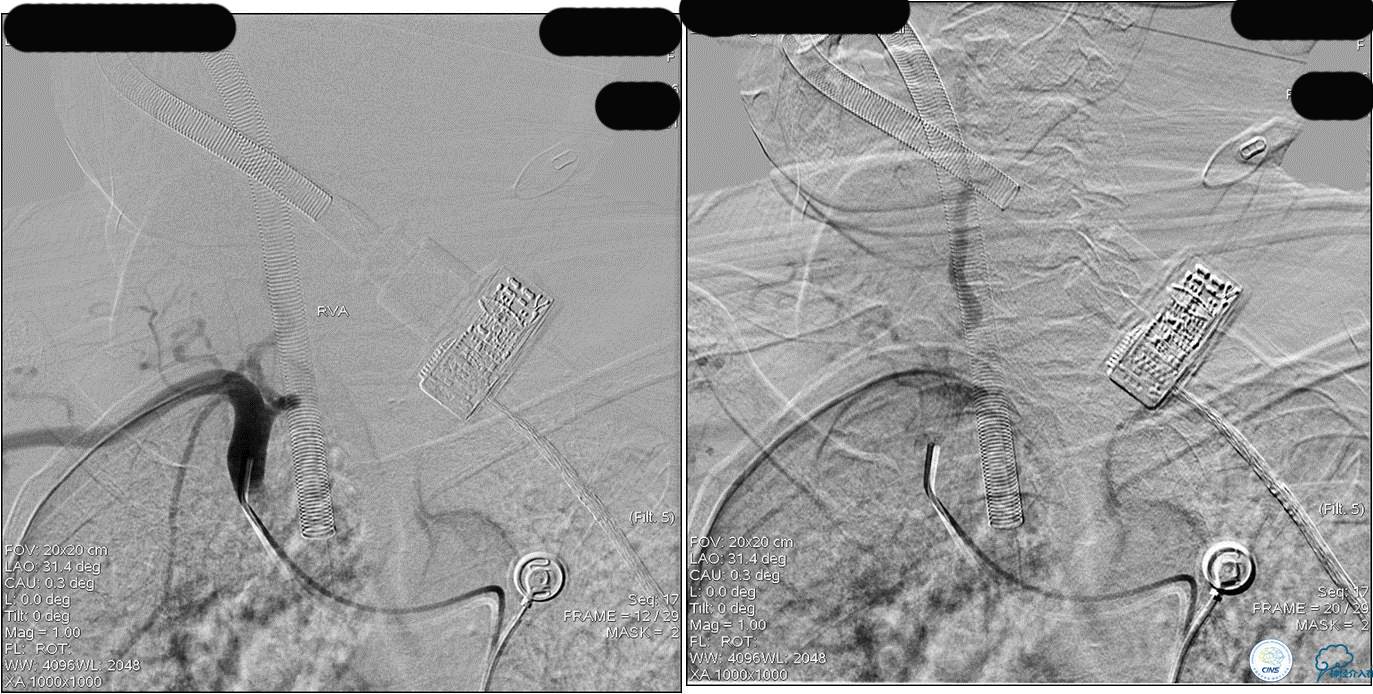

》DSA资料(第3次取栓)

第3次取出血栓

》DSA资料(第3次取栓后,发病10h)

》DSA资料(观察30min后,左椎造影)